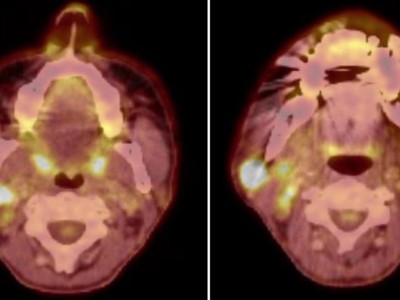

Neues in der Radiochemotherapie von Kopf-Hals-Tumoren

Erste Studien deuten darauf hin, dass eine Deeskalation der Radiochemotherapie bei nichtmetastasierten Kopf-Hals-Tumoren möglich ist – insbesondere bei HPV-positiven Karzinomen. Hypoxiesensitive Bildgebung könnte die Patientenselektion unterstützen. Gleichzeitig zeichnet sich die perioperative Checkpointinhibition als potenzieller neuer Standard bei resektablen HNSCC ab.

Eine ältere Frau schaut in die Ferne/© RgStudio / Getty Images / iStock (Symbolbild mit Fotomodell), Bestrahlungsplans einer Wirbelsäulenmetastase eines oligometastasierten Prostatakarzinoms/© Springer Medizin Verlag GmbH, Immuncheckpointinhibitoren binden an Krebszelloberflächenproteine /© Juan Gärtner / stock.adobe.com, Arzt misst Blutzucker per Glucometer/© geargodz / Stock.adobe.com (Symbolbild mit Fotomodell), Ein Anatomie-Modell des Kopfes in der HNO-Praxis/© peakSTOCK / Gettty Imgaes / iStock (Symbolbild mit Fotomodellen), Larynxkarzinom/© Springer Medizin, Tropf in Krankenhaus/© Amornrat Phuchom / Getty Images / iStock, Infusionstropf im Krankenhaus /© Trsakaoe / stock.adobe.com, Zytologischer Abstrich bei gynäkologischer Untersuchung/© Iryna / stock.adobe.com (Symbolbild mit Fotomodell), Pembrolizumab-Modell (Illustration)/© Kateryna_Kon / stock.adobe.com, Plattenepithelkarzinom des Oropharynx/© Springer Medizin Verlag GmbH, Tumor im linken Kleinhirnbrückenwinkel und inneren Gehörgang (linkes Bild) und Tumor am Foramen jugulare (rechtes Bild)/© Springer Medizin, Frau erhält Infusion/© Eakkachai / Stock.adobe.com (Symbolbild mit Fotomodell), Raumforderung im Ohr/© Franzen A M und Coordes A / all rights reserved Springer Medizin Verlag GmbH, Blumenkohlartiger Knoten am Hinterkopf/© Winkler D. et al. doi.org/10.1007/s00105-024-05437-1 unter CC-BY 4.0, 18-FDG-PET-Fusions-CT vom Kopf/© Sheila Büchel u. Markus Jungehülsing doi.org/10.1007/s00106-024-01459-2 unter CC-BY 4.0, VMAT-Bestrahlungsplan einer definitiven Radiochemotherapie eines linksseitigen, lokal fortgeschrittenen Tonsillenkarzinoms/© Schnellhardt, S et al. / all rights reserved Springer Medizin Verlag GmbH, Search Icon, Einem Mann wird Blut abgenommen/© auremar / stock.adobe.com (Symbolbild mit Fotomodellen), Frau wird Blut abgenommen/© andresr / Getty Images / iStock (Symbolbild mit Fotomodellen), Eine Frau erhält eine Chemotherapie/© peopleimages.com / stock.adobe.com (Symbolbild mit Fotomodell)